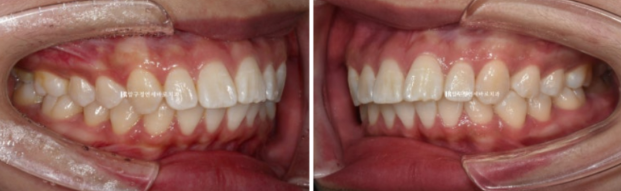

23.02~24.09

23.02

한 20대 젊은 환자분이 돌출입 교정을 위해 내원했습니다.

치아는 가지런한 편이고 어금니 교합도 좋지만 앞니 뻗침이 보입니다.

입이 잘 안 다물어지는 입술부전증이 보입니다.

입술에 힘을 빼고 있으면 치아가 보이도록 약간 벌어진 상태가 되는 것을 입술부전증이라고 합니다.

앞니 돌출이 해소되면 자연스럽게 좋아집니다.

치료계획은 작은 어금니 4개를 발치하고 돌출입을 확실히 개선하기로 했습니다.

클리피씨 장치를 선택하셨고 바로 교정 시작했습니다.

치료기간은 총 1년 7개월입니다.